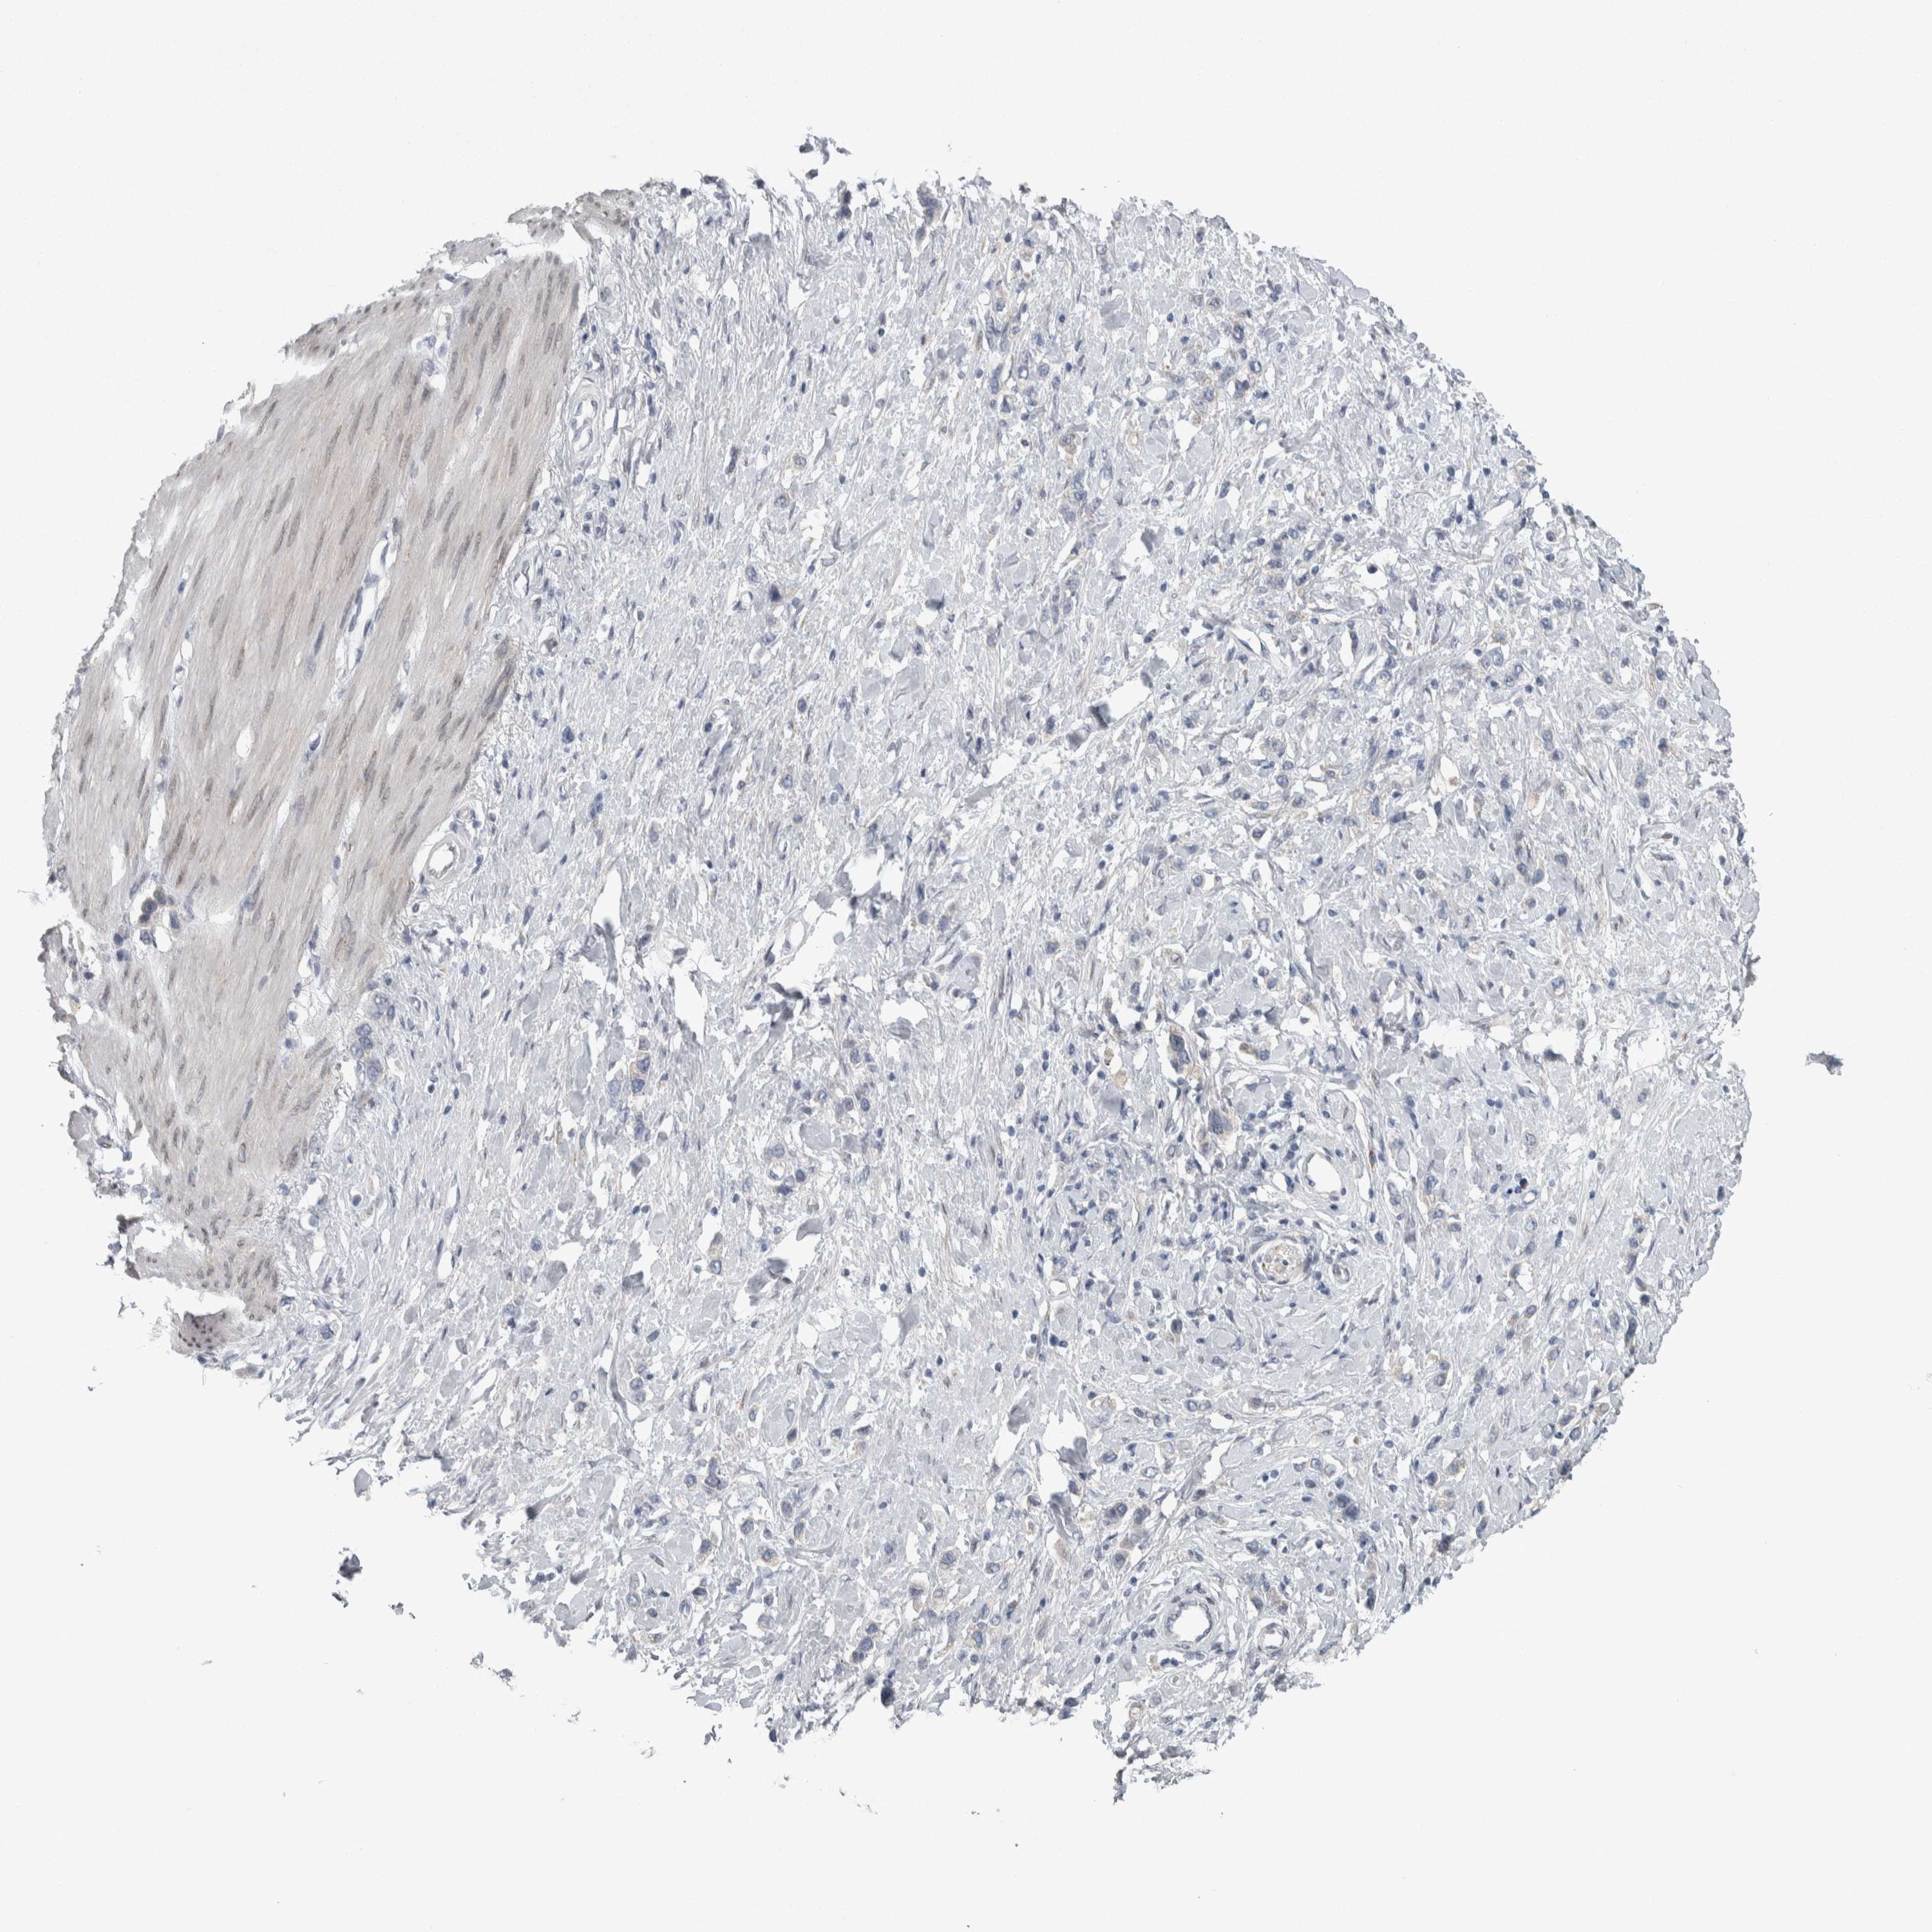

STOMACH CANCER - Protein expressioni

A mouse-over function shows sample information and annotation data. Click on an image to view it in a full screen mode. Samples can be filtered based on level of antibody staining by selecting one or several of the following categories: high, medium, low and not detected. The assay and annotation is described here.

Note that samples used for immunohistochemistry by the Human Protein Atlas do not correspond to samples in the TCGA dataset.

Antibody stainingi

Antibody staining in the annotated cell types in the current human tissue is reported as not detected, low, medium, or high, based on conventional immunohistochemistry profiling in selected tissues. This score is based on the combination of the staining intensity and fraction of stained cells.

Each image is clickable and will lead to virtual microscopy that enables deeper exploration of all samples and also displays staining intensity scores, fraction scores and subcellular localization as well as patient and tissue information for each sample.

Antibody HPA018002

Antibody HPA024071

Antibody CAB013470

Staining

High

Medium

Low

Not detected

Intensity

Strong

Moderate

Weak

Negative

Quantity

>75%

75%-25%

<25%

None

Location

Nuclear

Cytoplasmic/membranous

Cytoplasmic/membranous,nuclear

Adenocarcinoma, NOS

Adenocarcinoma, High grade